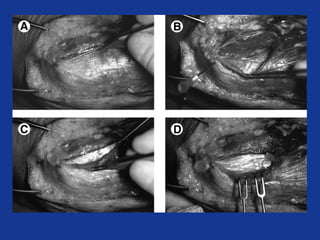

Open release

• Incision ant to lateral epicondyle

• ECRL posterior fascial edge lifted

• Degenerate tissue within ECRB excised

• Defect firmly repaired

– +/- suture anchors

• ?Decompression of PIN

• Excellent / good 75 – 91%

• Poor / failed 2 – 11%

• 80 – 95% return to normal activity in 4/12

ECRL

EDC

L. Cond

ECRB

Scratch maneuver